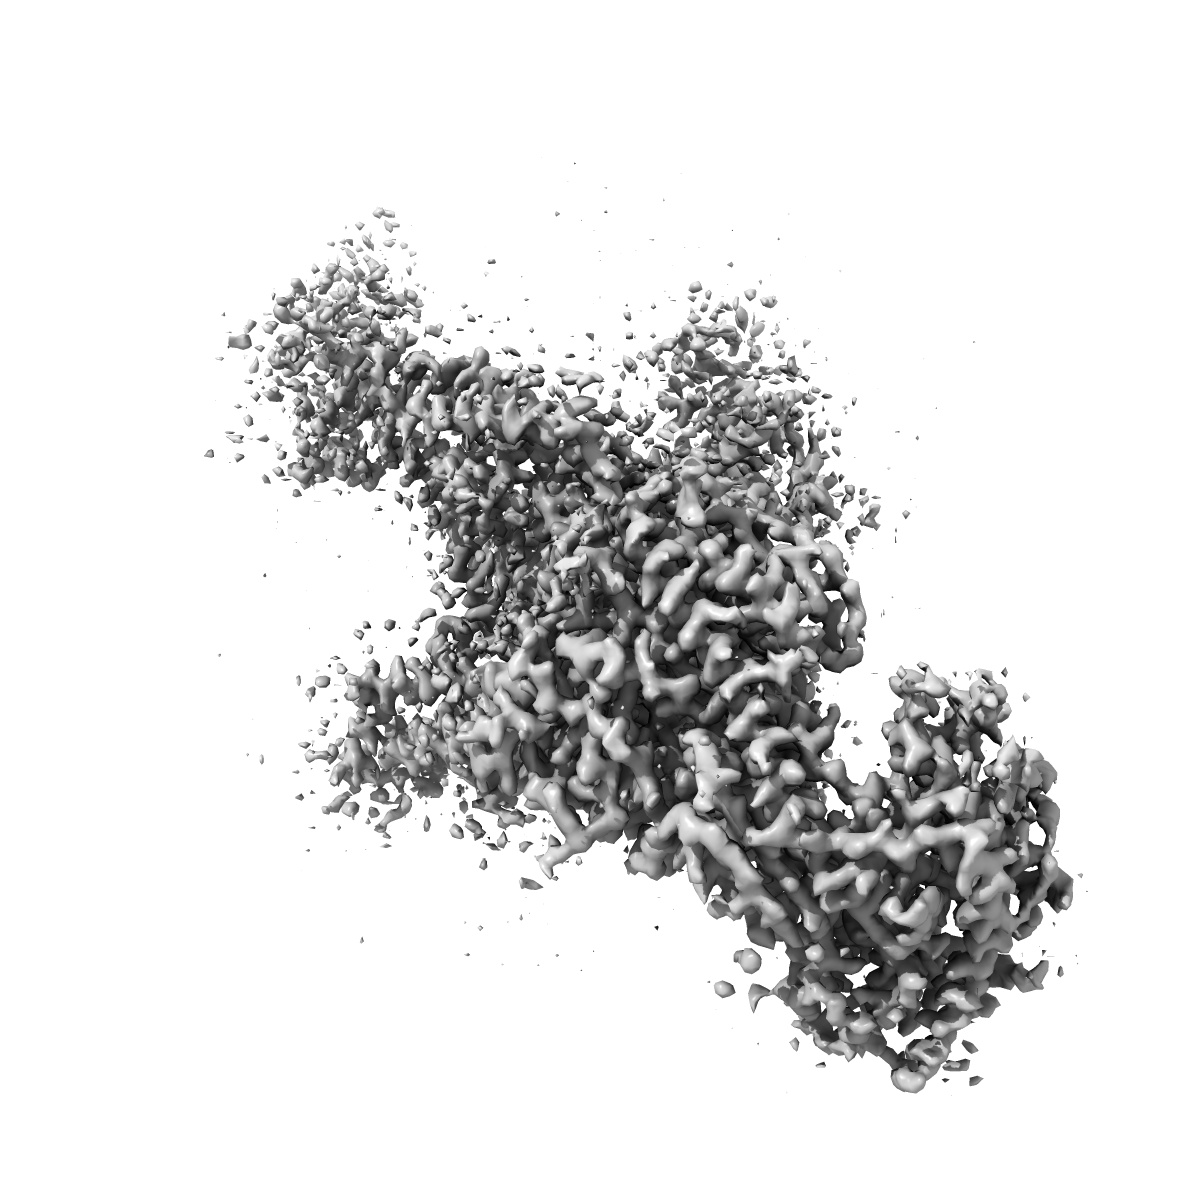

Human L-type voltage-gated calcium channel Cav1.2 in the presence of amiodarone and sofosbuvir at 3.3 Angstrom resolution

Structural basis for human Ca v 1.2 inhibition by multiple drugs and the neurotoxin calciseptine.

Gao S, Yao X, Chen J, Huang G, Fan X , Xue L , Li Z, Wu T , Zheng Y, Huang J, Jin X, Wang Y, Wang Z, Yu Y, Liu L, Pan X, Song C, Yan N

(2023) Cell , 186 , 5363 - 5374.e16